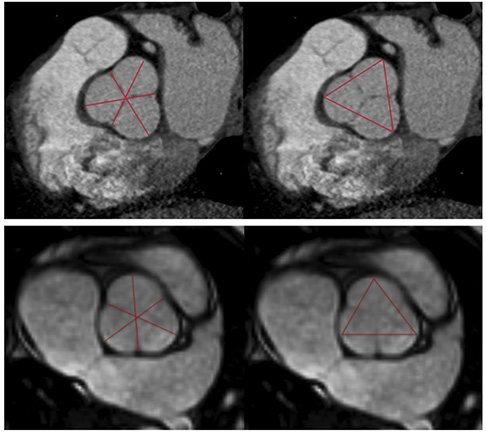

L'imagerie en coupe permet une mesure plus précise des diamètres aortiques, le caractère asymétrique de l'aorte pouvant parfois entraîner une sous-estimation de celui-ci en échocardiographie. L'IRM et le scanner peuvent être tous les deux utilisés (20). L'IRM a l'avantage de ne pas être irradiante. On utilisera des séquences SSFP (Steadystate free precession) permettant une bonne différenciation entre les compartiments liquidiens et les tissus alentours et ainsi visualiser correctement la lumière aortique. Le scanner synchronisé au rythme cardiaque est irradiant mais permet des mesures plus précises que l'IRM du fait de son excellente résolution spatiale. Il faudra utiliser le mode double oblique pour s'aligner parfaitement avec l'aorte dans tous les plans. Les mesures sont réalisées en petit axe de fond de cusp à commissure ou de fond de cusp à fond de cusp (plus grand diamètres) (Figure 4). Le scanner permet également d'étudier l'anatomie de la valve aortique et de rechercher des lésions coronaires pour les patients éligibles à une intervention (Figure 5).

Figure 5 .

Mesure des diamètres des sinus de valsalva en scanner (haut) et en IRM (bas) de fond de cusp à commissure (gauche) et de fond de cusp à fond de cusp (droite).